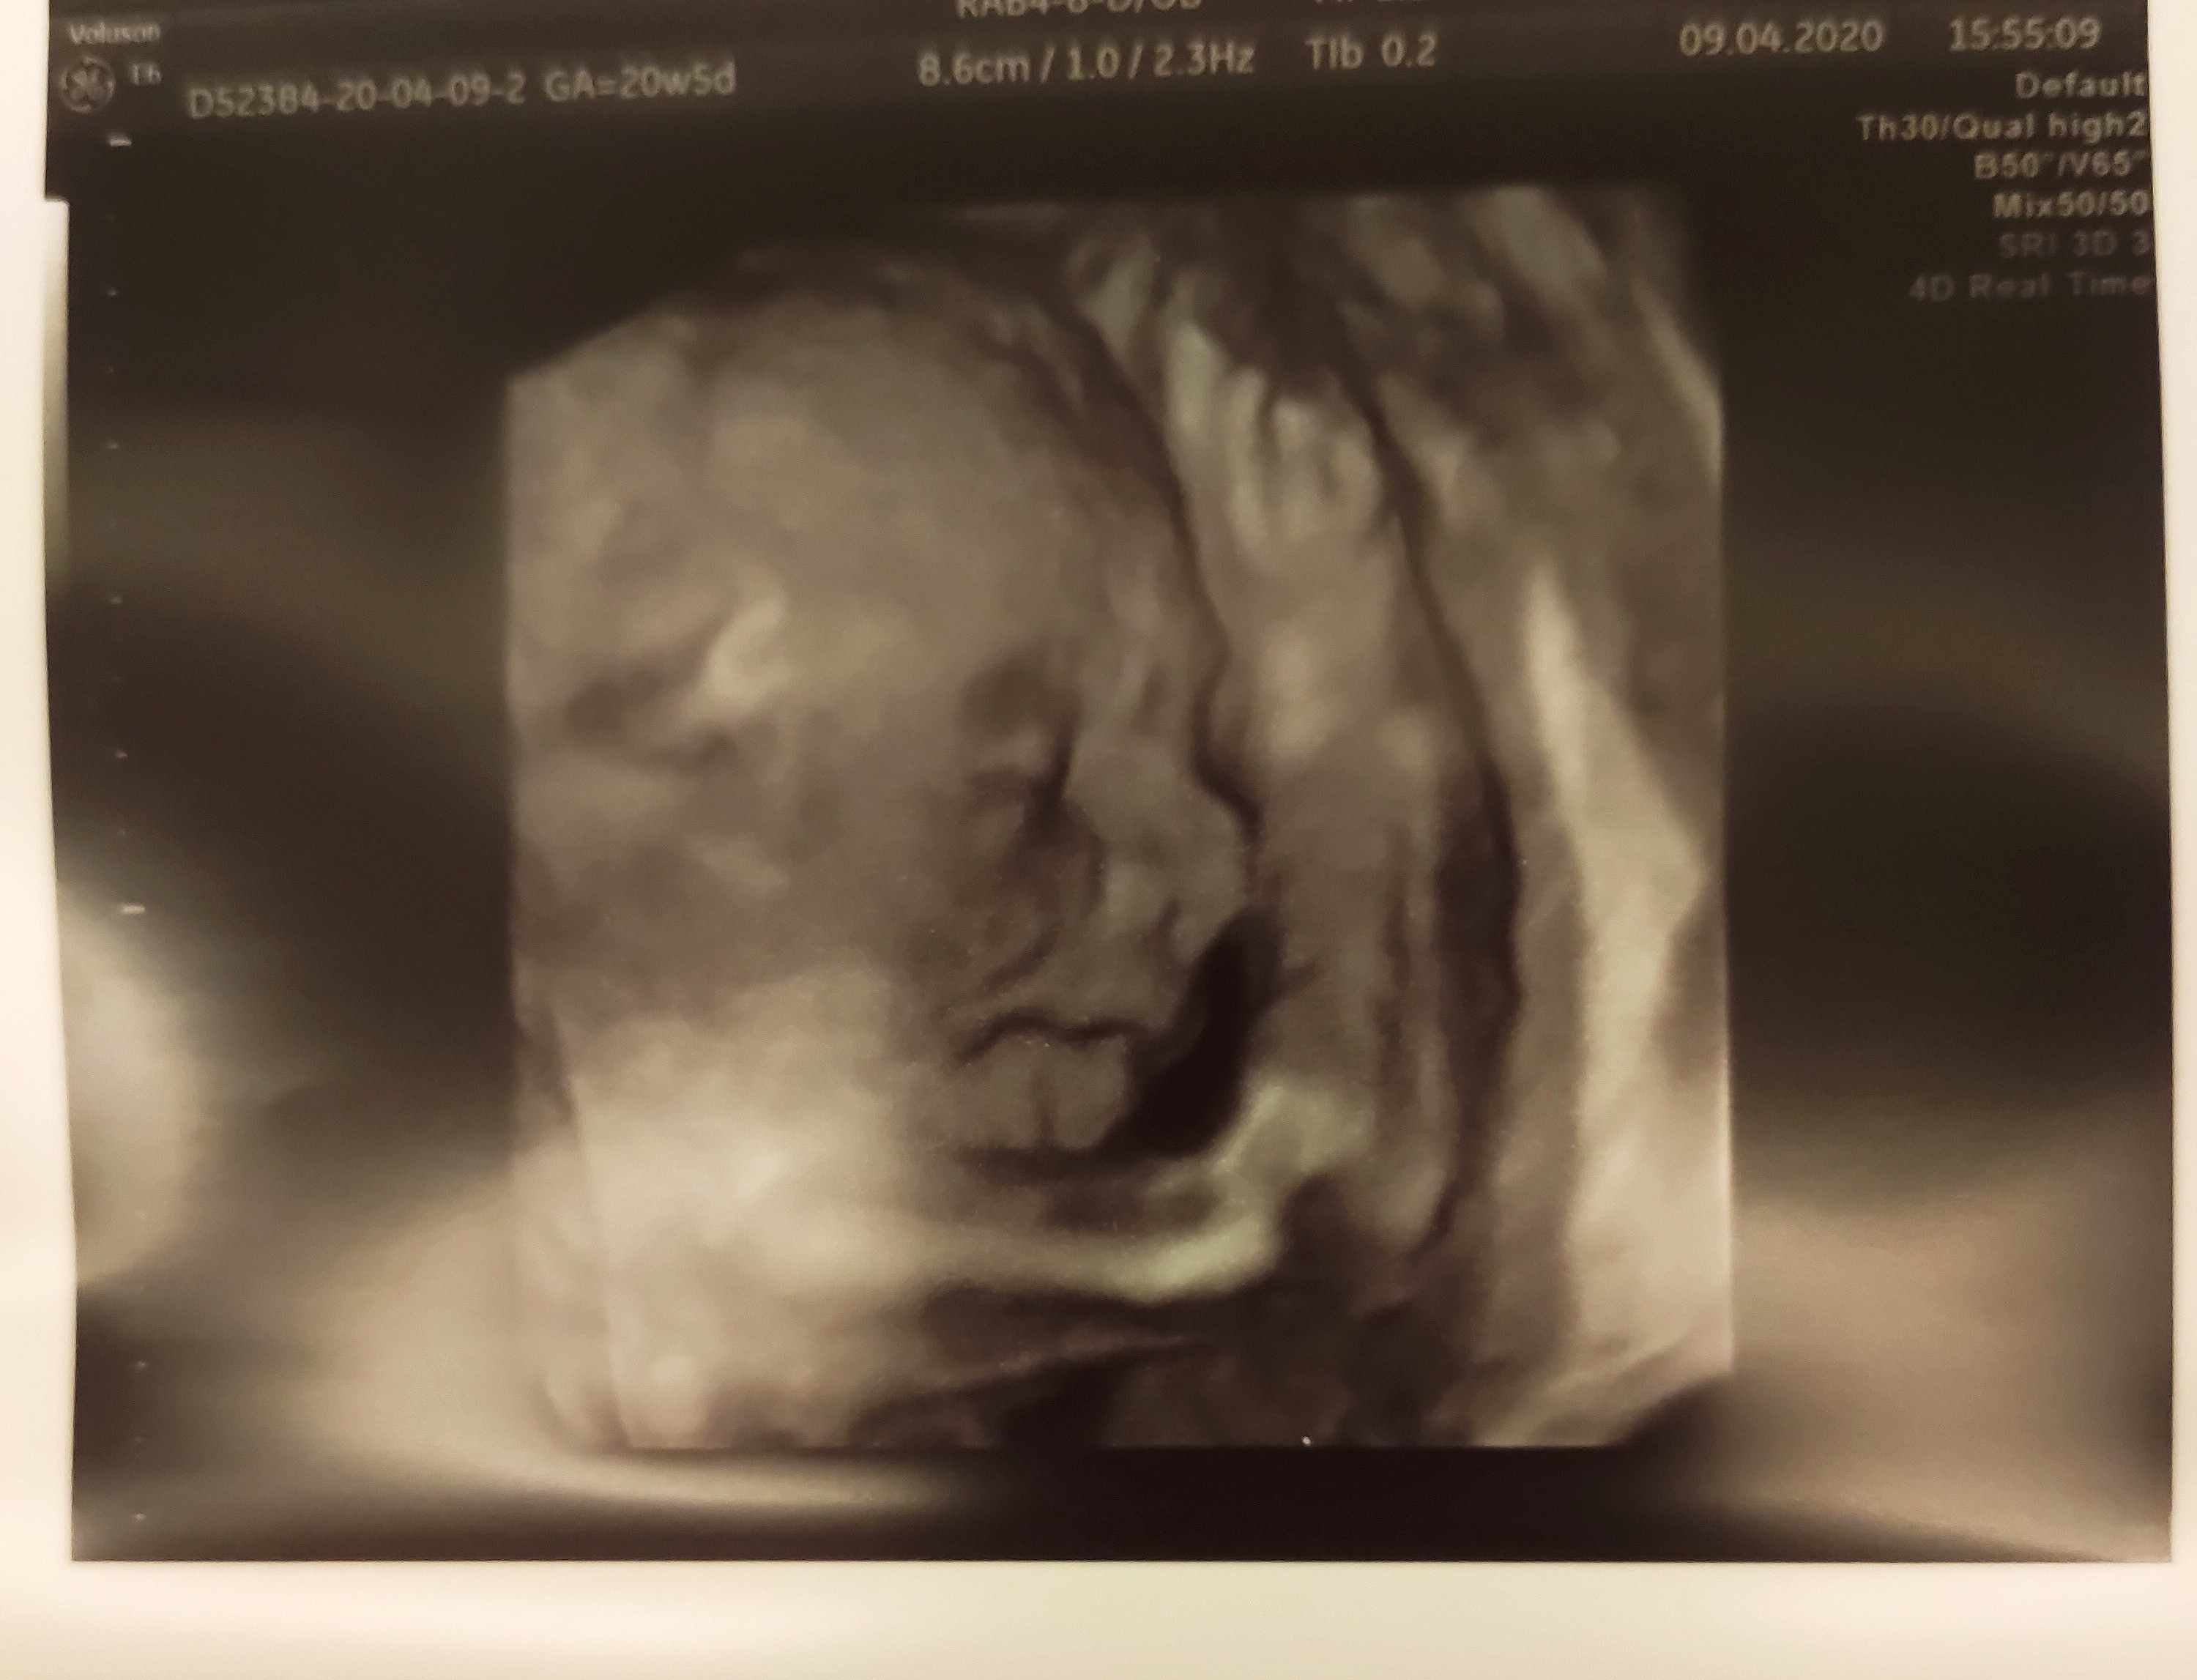

A ja się melduję po połówkowym.

U Kubusia wszystko wporządku, budowa anatomiczna dzidziusia książkowa, przepływy wszystkie prawidłowe. Dziś 20TC+5 i ważymy już 416gram 🥰

Najlepsze, że jak tylko lekarz przyłożył głowice do brzucha pytał czy znamy płeć, a my mówimy że tak na co lekarz: pierwsze co na USG pokazał to co ma między nogami 😅 także mało wstydliwe moje dziecko 🙄 uff...

A Kubuś się do Was ze zdj nieśmiało uśmiecha 🙂

Jestem szczęśliwa ♥